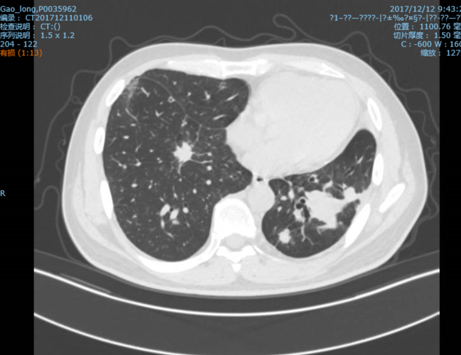

2017.12.12:

第9次PD CT:双肺结节增多增大, PD; 腹盆腔MRI: SD

影像学检查:

左主支气管腔内新生物电圈套及APC +肺转移灶SBRT

2017-10-23 治疗前:

2017-12-11 治疗后: